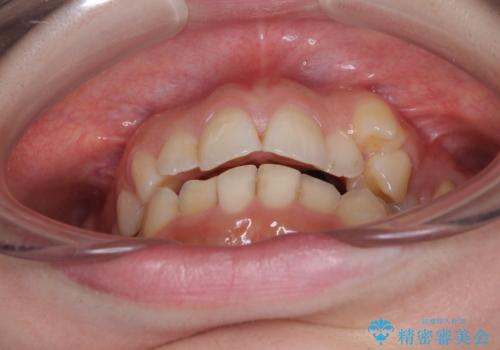

顕著な八重歯をインビザラインで治せるところまで改善

- 顕著な八重歯など、上下前歯のデコボコとスペースを気にして来院された患者様です。

八重歯改善には第一小臼歯の抜歯が必要であり、移動量が多いことから補助装置により八重歯を引き込むこととしました。

補助装置だけでなく、部分的にワイヤー矯正も使用しましたが、上下のスペースは改善しきれず、側切歯(前から2番目の歯)や顕著な八重歯は、インビザラインで治療するには限界があることがよく分かりました。

より良い仕上がりを希望される場合には、ワイヤー装置による矯正治療がお勧めとなります。